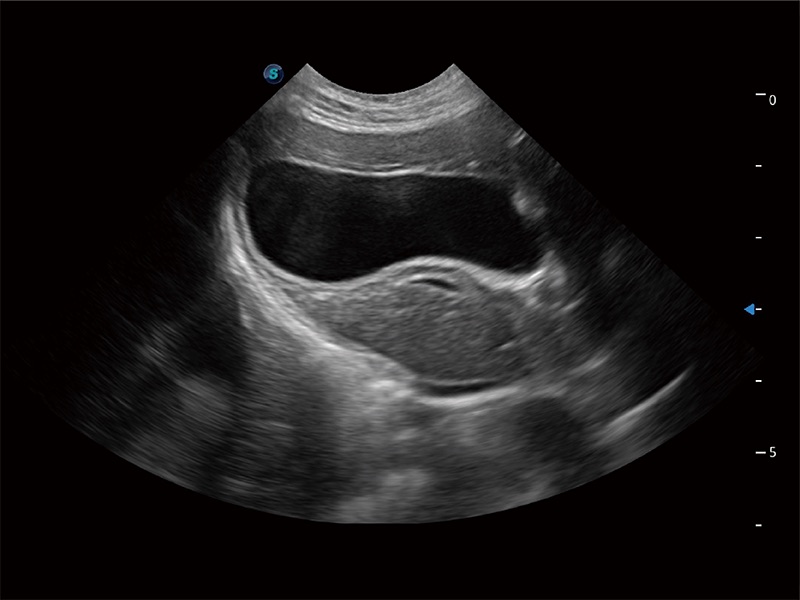

高性能和先进的临床应用工具可以为动物医生提供临床信心。ProPet 80 搭载了先进的腹部和浅表应用工具,帮助医生在日常临床实践中发挥前所未有的作用。

ProPet 80 专为动物医生设计,对不同的动物体型和生理结构作出了针对性的优化。通过动物影像专用软件,可满足个性化的应用需求,帮助动物医生获得更精确的诊断数据。

为精细结构及组织边缘提供高清晰度的图像和更大的成像视野。帮助减轻医生的用眼疲劳,快速精准获得测量的数据。